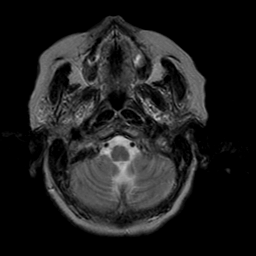

Stroke:T2-weighted MR #2 -- Slice #2

[Home][Help][Clinical] Slice 2